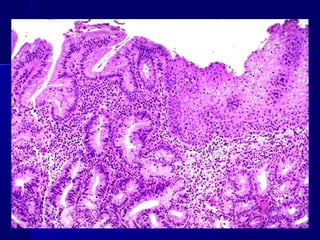

Hyperplasia

METAPLASIAMETAPLASIA

 Es una alteración reversible en la que un tipoEs una alteración reversible en la que un tipo

celular maduro es sustituido por otro (epitelial ocelular maduro es sustituido por otro (epitelial o

mesenquimatoso)mesenquimatoso)

 Ejemplos: metaplasia escamosa, Esófago deEjemplos: metaplasia escamosa, Esófago de

Barret.Barret.

1. Metaplasias epiteliales:

Metaplasia epitelial escamosa: mucosas, conductos,

bronquios, cervix, endometrio y próstata.

Metaplasia epitelial apocrina: glándulas exocrinas de

la mama.

Metaplasia intestinal: En las gastritis y colecistitis

crónicas y esófago de Barrett.

Metaplasia antral: En la vesícula biliar y cuerpo

gástrico.

Las metaplasias tienen un remoto carácter

premaligno por:

1. Las mismas causas pueden producir metaplasias y

tumores.

2. Sobre áreas de metaplasia aparecen con

frecuencia displasias y carcinomas.

3. Algunos tumores solo aparecen sobre tejidos

metaplásicos.